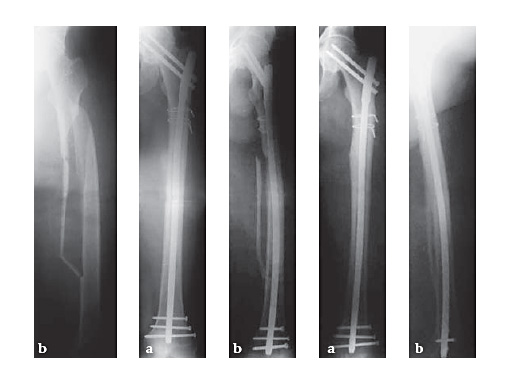

34-year-old malepolytraumatraffic accidentAO Classification 32-C3

Case provided by Hermann Bail, Berlin, DE